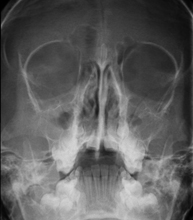

Técnica mediante la cual, utilizando rayos X, se obtienen imágenes del cráneo para su estudio. Indicaciones: traumatismo, cierre precoz de suturas craneales. - RX Senos Paranasales

Técnica mediante la cual, utilizando rayos X, se obtienen imágenes de los senos paranasales para su estudio. Indicaciones: dificultad respiratoria nasal, tos crónica, cefalea, mucosidad. - RX ATM (Articulación Temporo-Mandibular)

- Paranasal Sinuses X-ray

This technique uses X-ray rendered imaging for examining the paranasal sinuses. Indicated for: headache, chronic cough.